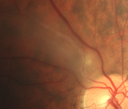

Vasoproliferative Tumor 7 Years after Retinal Detachment Repair519 views65 year old female presents 7 years following retinal detachment repair with peripheral white mass with hemorrhage.Mar 07, 2020

Vasoproliferative Tumor 7 Years after Retinal Detachment Repair474 views65 year old female presents 7 years following retinal detachment repair with peripheral white mass with hemorrhage.Mar 07, 2020

Vasoproliferative Tumor 7 Years after Retinal Detachment Repair451 views65 year old female presents 7 years following retinal detachment repair with peripheral white mass with hemorrhage.Mar 07, 2020